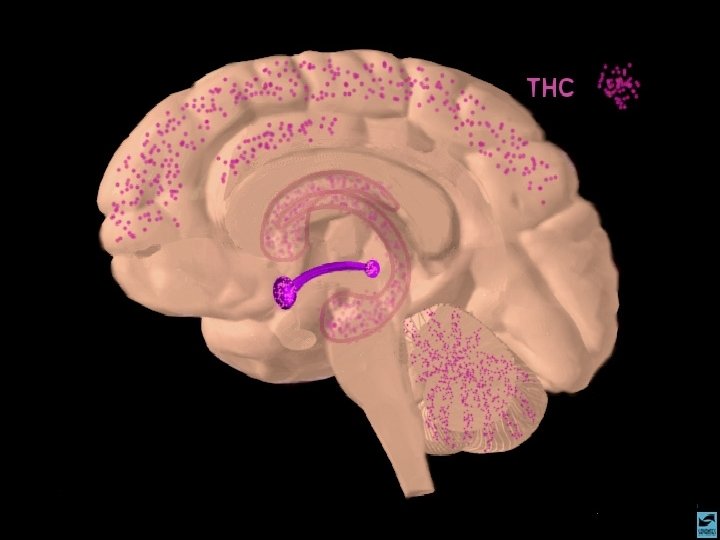

MACONHA TETRAHIDRO CANABINOL EFEITOS CEREBRAIS 1 - DISTRIBUI-SE RAPIDAMENTE POR TODO O CÉREBRO 2 - TEM AFINIDADE COM O RECEPTOR FORMADO AMANDAMIDA, QUE EXISTE NO HIPOCAMPO, TRONCO CEREBRAL E TRATO PÁLIDO 3 - AGE COMO NEUROMODULADOR ALTERANDO A PRODUÇÃO DE UM SEGUNDO MENSAGEIRO REGULADO POR OUTRO NEUROTRANSMISSOR